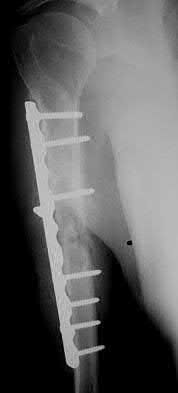

3. # Which of the following is not an appropriate implant for treatment of the fracture seen in Figure A?

5. Sliding hip screw Corrent answer: 5

The image shows a reverse obliquity intertrochanteric hip fracture.

According to the referenced article by Haidukewych et al, unstable peritrochanteric hip fractures have a worse outcome (failed in 9/16 cases) if treated with a sliding hip screw. Two additional factors that were found to have a strong correlation with postoperative failure (nonunion, loss of reduction) were poor reduction and poor implant placement. In this study, fixed angle devices were superior. Intramedullary fixation has the added advantage of a shorter lever arm and less potential for fracture collapse and limb shortening.

The IMN also acts as a medial buttress.

According to Sanders et al, the dynamic condylar screw (DCS) can also be used in subtrochanteric models, but should not be used if extensive comminution is seen, as they reported a high failure rate with DCS in these fractures if highly comminuted. They report a 77% overall union rate with this device.